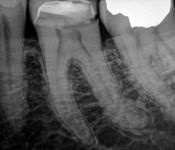

Pictured: Necrosis and 3 Year Recall with Complete Root Formation after Revascularization

Our patient developed necrosis of tooth #9 caused by intrusive luxation. We opted to treat with revascularization with triple antibiotic and MTA. In our 3 year recall, the patient had achieved complete root formation.